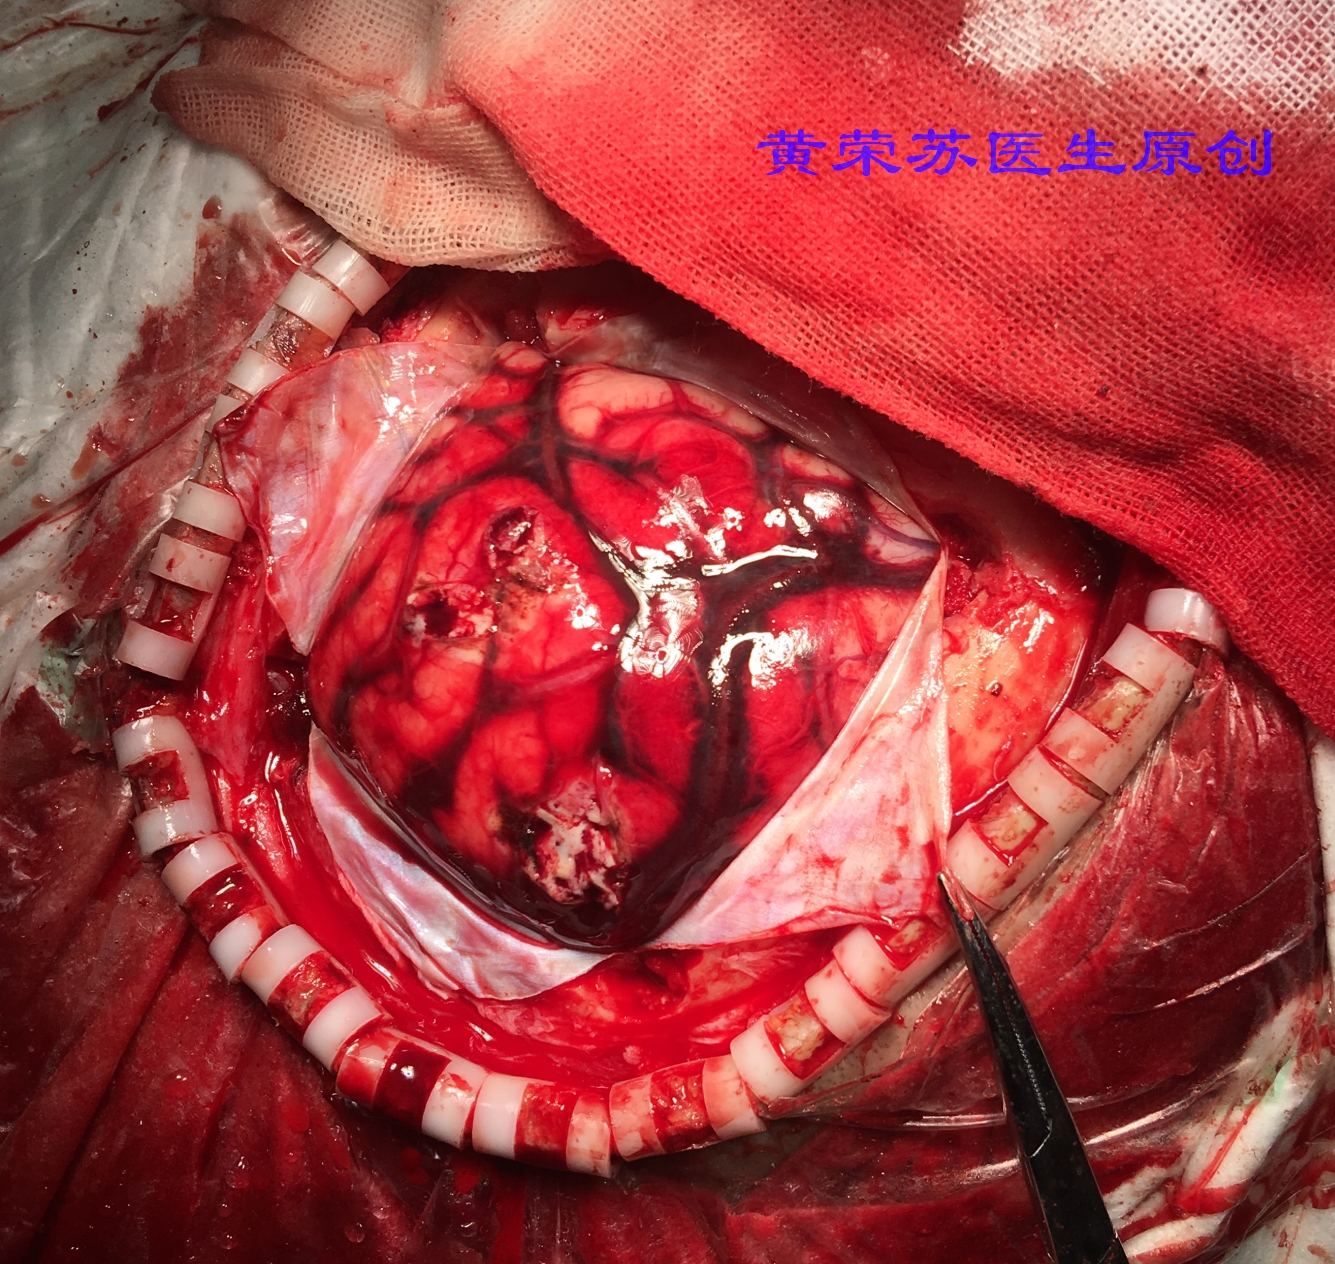

6、蛛网膜下腔出血:是指脑底部或脑表面的病变血管破裂出血,血液直接流入蛛网膜下腔所致,其中微型动脉瘤破裂是蛛血最常见的原因。表现为突发起病,以剧烈头痛为最常见的起病方式,其次还伴有恶心、呕吐和脑膜刺激征。

图八、术中所见蛛网膜下腔出血